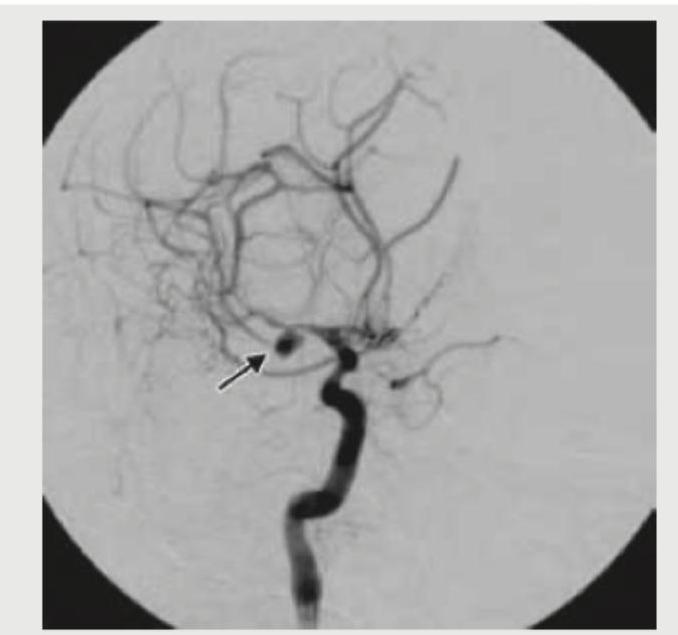

The digital subtraction angiography given below shows? (AIIMS Nov 2017)

Question 1: The digital subtraction angiography given below shows? (AIIMS Nov 2017)

- A. Intra-cranial pseudo-aneurysm

- B. Carotid-cavernous fistula (Correct Answer)

- C. Angiofibroma tumor blush

- D. Vein of Galen malformation

Explanation: ***Carotid-cavernous fistula*** - The image shows early opacification of the **cavernous sinus** and cerebral veins (indicated by the arrow) directly from the internal carotid artery, which is characteristic of a carotid-cavernous fistula. - This high-flow shunt between the arterial and venous systems leads to venous congestion and often presents with **pulsatile exophthalmos**, chemosis, and ophthalmoplegia. *Intra-cranial pseudo-aneurysm* - A pseudo-aneurysm typically appears as a sac-like outpouching from an artery, lacking a true vessel wall, and would not show direct early venous filling. - Pseudo-aneurysms are often caused by **trauma** or infection and may present with signs of hemorrhage if ruptured. *Angiofibroma tumor blush* - An angiofibroma would appear as a **hypervascular mass** with a dense, persistent tumor blush on angiography, but it would not show early direct shunting into veins. - These tumors are typically found in the nasopharynx and present with symptoms like **epistaxis** and nasal obstruction. *Vein of Galen malformation* - A **Vein of Galen malformation** is a developmental anomaly involving an arteriovenous fistula that drains into a dilated median prosencephalic vein, often presenting in infants with high-output heart failure. - While it is an arteriovenous malformation, its typical location and presentation are different from the findings shown in this image, which demonstrates shunting in the region of the cavernous sinus.